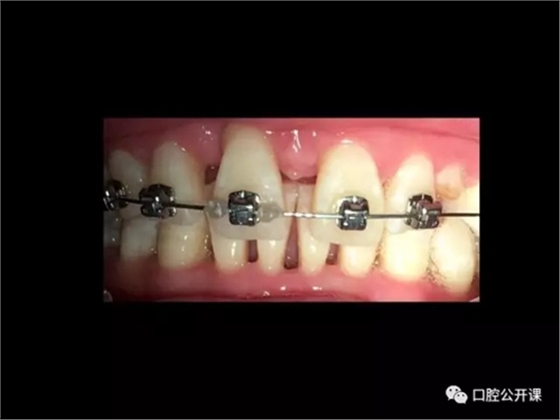

楊淑銀醫(yī)師用他的一例侵襲性牙周炎五年臨床病例追蹤來(lái)縮影一個(gè)青年牙周醫(yī)師的成長(zhǎng)之路,帶我們一起探索看似平凡枯燥的牙周基礎(chǔ)治療到底有怎樣的重要性?